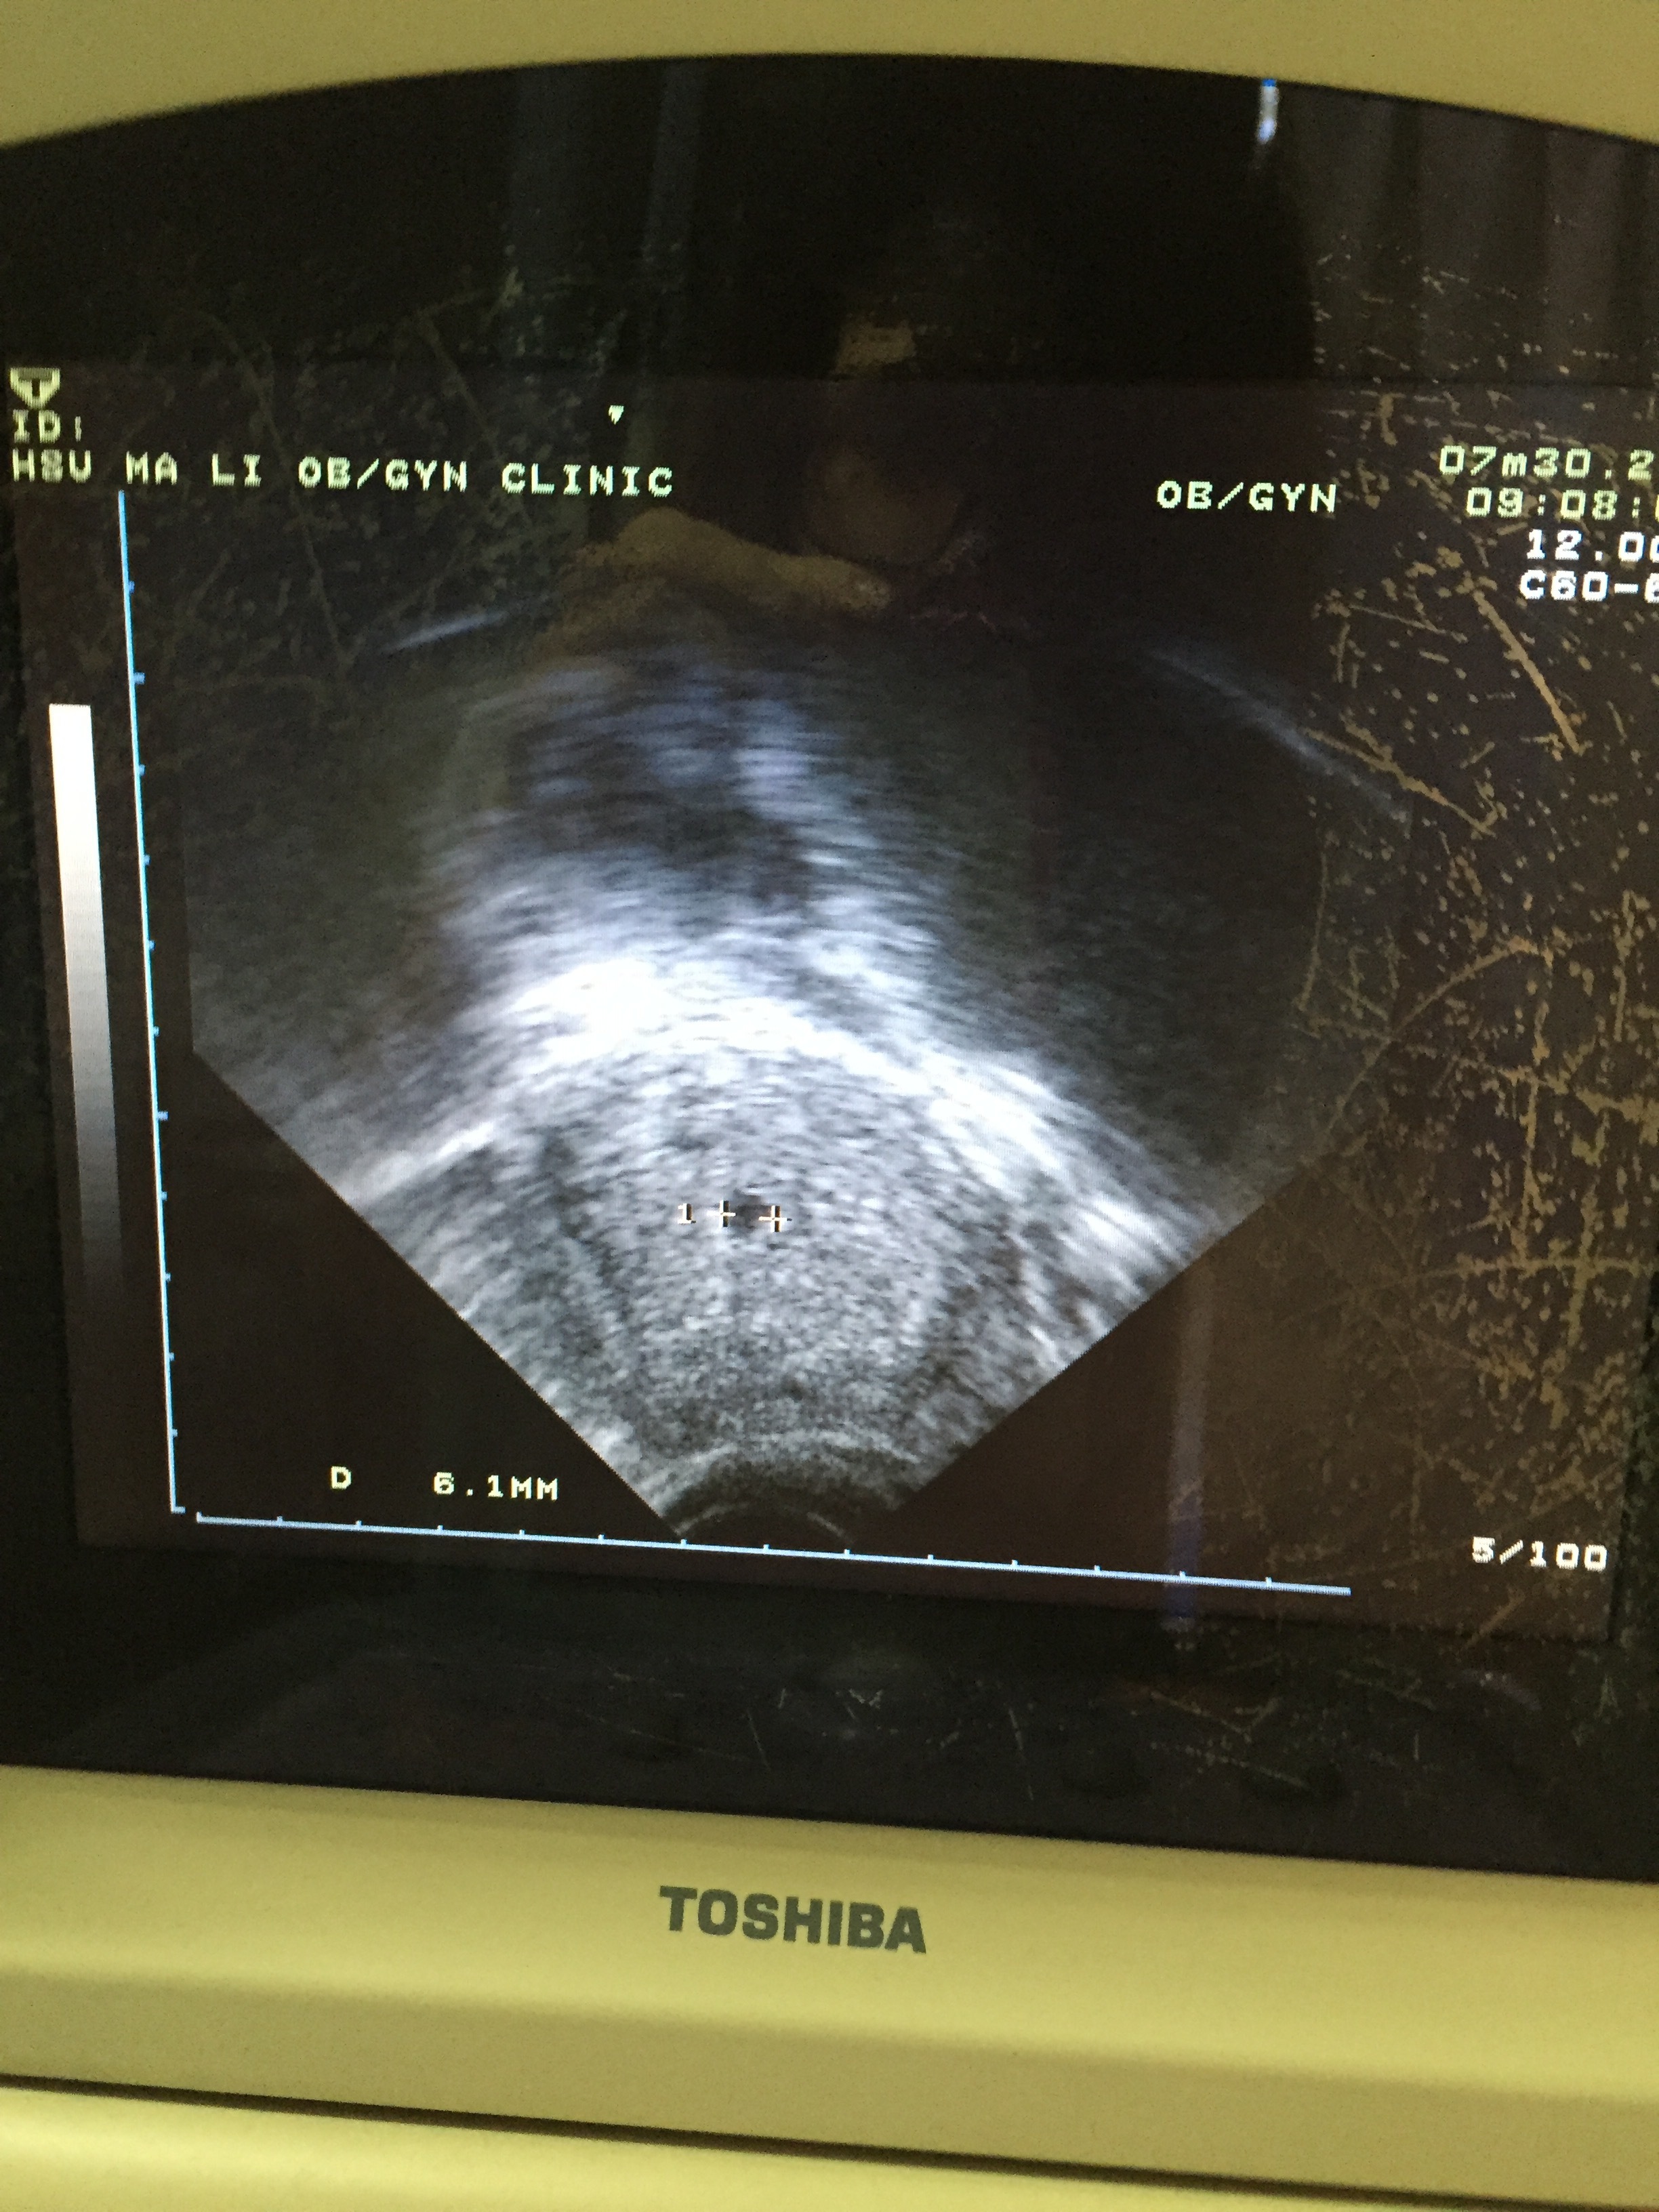

懷孕五週一天

大家好!最後一次月經來6/23,7/23驗到兩條線,昨天7/30去婦產科驗尿也是馬上兩條線,不過腹超照不到,後來醫生跟我說怕子宮外孕,要我驗血,回家很害怕,擔心一整晚,今天去另外一家婦產科看,一樣腹超照不到,醫生決定陰道超音波,找了一下有找到疑似小黑點,不過只有0.6mm, 醫生說有可能是胚胎 不過還太小,但也不敢說絕對排除子宮外孕的可能,想請問大家五週腹超照的到嗎?大小多少呢?子宮外孕可能性大嗎?謝謝!附上今天陰道超音波照到的小黑點